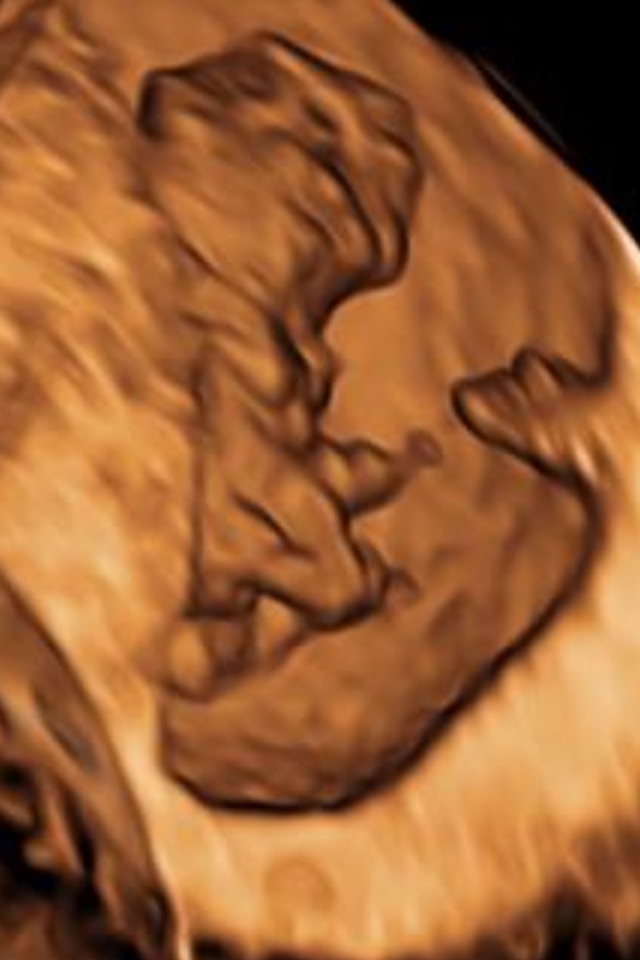

Sorry 9 weeks is a little too early to determine gender. A scan after 12 or 13 weeks can give you best results.